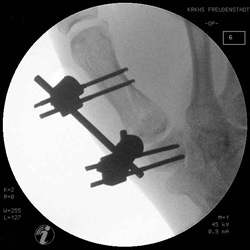

Mit einem Kirschnerdraht wird vorgebohrt und danach

die Schrauben plaziert. Zwei Schrauben in das Trapezium und zwei Schrauben

diestal der Fraktur.

Die Montage des Rahmens ist mit dem Microfixateur unproblematisch,

da die Fixateurteile sich ebenso leicht plazieren lassen, wie mit dem

Hoffmann II.